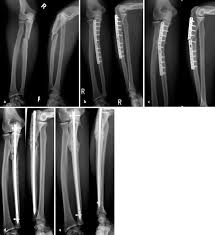

Bei den dabei verwendeten sogenannten Marknägeln handelt es sich meist um Implantate aus Titan oder Edelstahl. Die Diagnose Multiples Myelom in Deutschland fälschlicherweise oft mit dem solitären Plasmozytom gleichgesetzt löst Schock Angst und Ratlosigkeit aus. Es blieben subtrochantär große Löcher im Femur mit einer lateralen kortikalen Lücke von 12x12 mm und einer weiteren.

Immerhin wird das Bein bin zum Knochen geöffnet Gewebe und Muskeln durchtrennt und es verbleiben Löcher in den Knochen. Die Schraube im Schenkelhals ließ sich noch lösen die zwei Verriegelungsschrauben jedoch nicht - die Schraubenköpfe brachen ab die Gewinde wurden überbohrt und brachen wieder ab. Da die Drähte bei auch nur leichter Lockerung eine Gefahr für Strecksehen darstellen gibt es sehr gute Gründe die Kirschnerdrähte zu entfernen.

Gelegentlich ist es nicht möglich das Material vollständig zu entfernen so dass es auch vorkommen kann dass Reste des Metalls im Körper belassen werden müssen. Ich habe neulich das Gleiche bei einem Schrank erlebt. Die Stabilität sollte nach der Entfernung kein Problem sein weil die Schrauben und Nägel immer versetzt angeordet sind also die Löcher nie über- untereinander lägen. Die ist hart und sehr spitz und lässt sich nicht bewegen. Sollten Metallteile weggebrochen sein werden die dann auch im Knochen belassen die tun nix. Hier ist die Radiusfraktur nicht mit einer Platte sondern mit Kirschnerdrähten erfolgt. Obwohl ein Schraubenloch noch lange im Röntgenbild nachweisbar ist kommt es zu einer fortschreitenden Geflechtknochenbildung die die Stresskonzentration im Schraubenloch zunehmend herabsetzt. Hierbei wird in manchen Fällen lediglich die einzelne Stellschraube entfernt wobei die komplette Metallentfernung ungefähr nach einem Jahr beginnt. Auch nach einem Jahr kann man im Röntgenbild nach einer Schraubenentfernung die Schraubenkanäle gut erkennen.